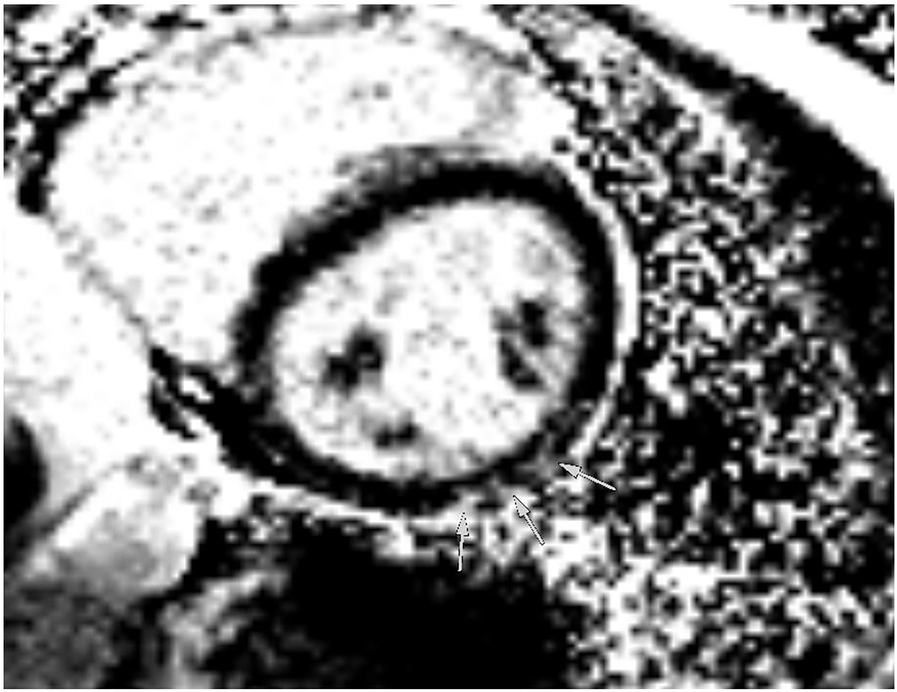

The athlete was lost to follow-up for 1 year (between 19 and 20 years of age), but another echocardiogram, performed at the age of 20 years, showed a slight decline of biplanar LVEF to 58%. However, the athlete had normal diastolic function and no signs of structural heart disease (Figures 5A,B). Strain analysis showed that the athlete’s global longitudinal strain was within the normal range (−22.3%), with reduced values in the inferolateral, inferior, and inferoseptal areas (Figure 5C). Cardiac biomarkers (troponin and NTproBNP) were within the normal range. CMR imaging was performed again and showed reproducible, consistent LGE of the inferolateral wall without edema (Figure 6). However, LVEF had declined from 69% to 53% within 1 year (from age 19 to 20 years). The athlete had, of her own accord, resumed recreational sport activity between 19 and 20 years of age.

Figure 6. Magnetic resonance imaging at follow-up showing inferolateral late gadolinium enhancement illustrated by arrows in a short-axis view, corresponding to regions of reduced strain in echocardiography.